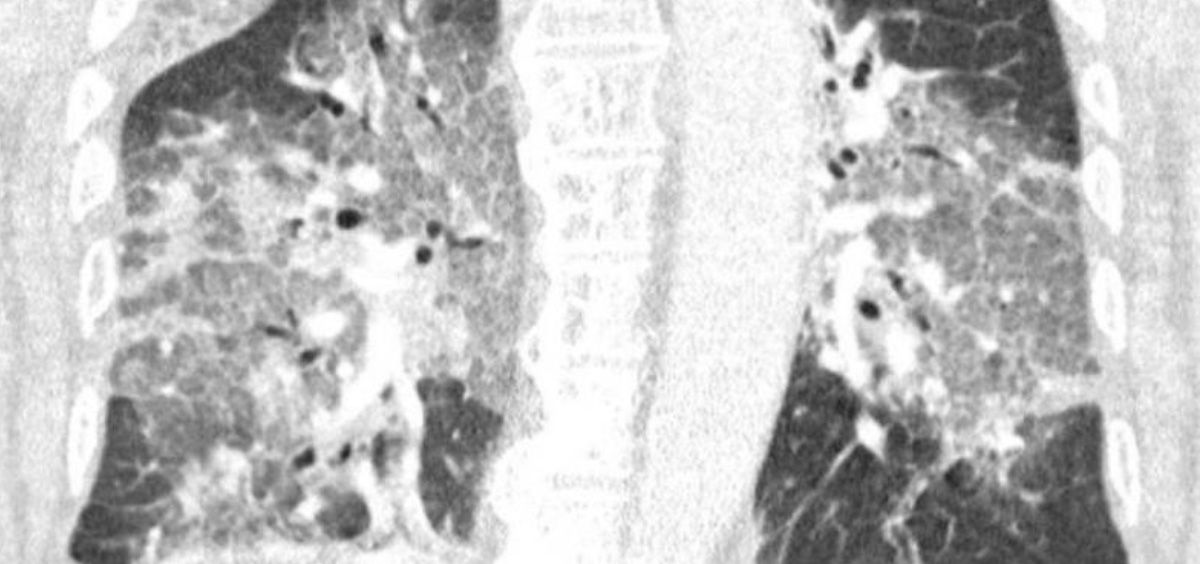

La acumulación de coronavirus en los pulmones es la responsable de las altas tasas de mortalidad por Covid-19, según han comprobado un equipo de investigadores de la NYU Langone Health (Estados Unidos) en un trabajo publicado en la revista 'Nature Microbiology'.

En concreto, el trabajo ha mostrado que las personas que murieron de COVID-19 tenían multiplicado por 10 la cantidad de virus, o carga viral, en las vías respiratorias inferiores, al igual que los pacientes gravemente enfermos que sobrevivieron a su enfermedad. Mientras tanto, los investigadores no encontraron evidencia que implique una infección bacteriana secundaria como la causa de las muertes, aunque advirtieron que esto puede deberse al curso frecuente de antibióticos administrados a pacientes críticamente enfermos.

A pesar de las preocupaciones anteriores de que el virus pueda provocar que el sistema inmunológico ataque el propio tejido pulmonar del cuerpo y provoque niveles peligrosos de inflamación, los investigadores no encontraron evidencia de que esto fuera un factor importante en las muertes por COVID-19 en el grupo estudiado. De hecho, señalan que la fuerza de la respuesta inmune parecía proporcional a la cantidad de virus en los pulmones.